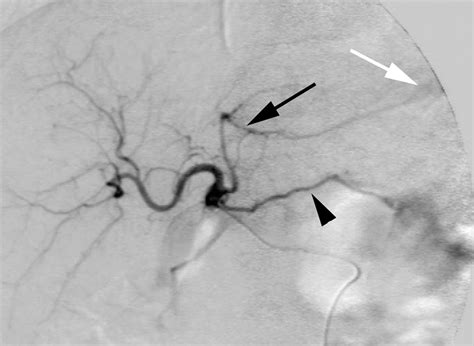

Imaging techniques play a vital role in evaluating the health and patency of the Left Gastric Artery. Computed Tomography (CT) scans with contrast enhancement are the gold standard for visualizing the vessel’s diameter and identifying any aneurysms or atherosclerotic changes. In cases of acute hemorrhage, angiography allows for both the diagnosis and immediate therapeutic intervention via transcatheter arterial embolization.

Diseases that affect the stomach often have a direct impact on its blood supply. Gastric ulcers, specifically those that erode into the Left Gastric Artery, represent a medical emergency due to the high-pressure flow within the vessel. Furthermore, gastric varices—which are dilated submucosal veins—can be associated with portal hypertension. In these patients, the blood flow dynamics within the LGA and its tributaries are often altered, potentially leading to increased risk of rupture and life-threatening hemorrhage.

Physicians must maintain a high index of suspicion for vascular involvement in patients presenting with hematemesis or melena. Early identification of the vessel status through diagnostic imaging can guide the treatment team toward the most effective management strategy, whether it be endoscopic clipping, surgical ligation, or endovascular embolization.